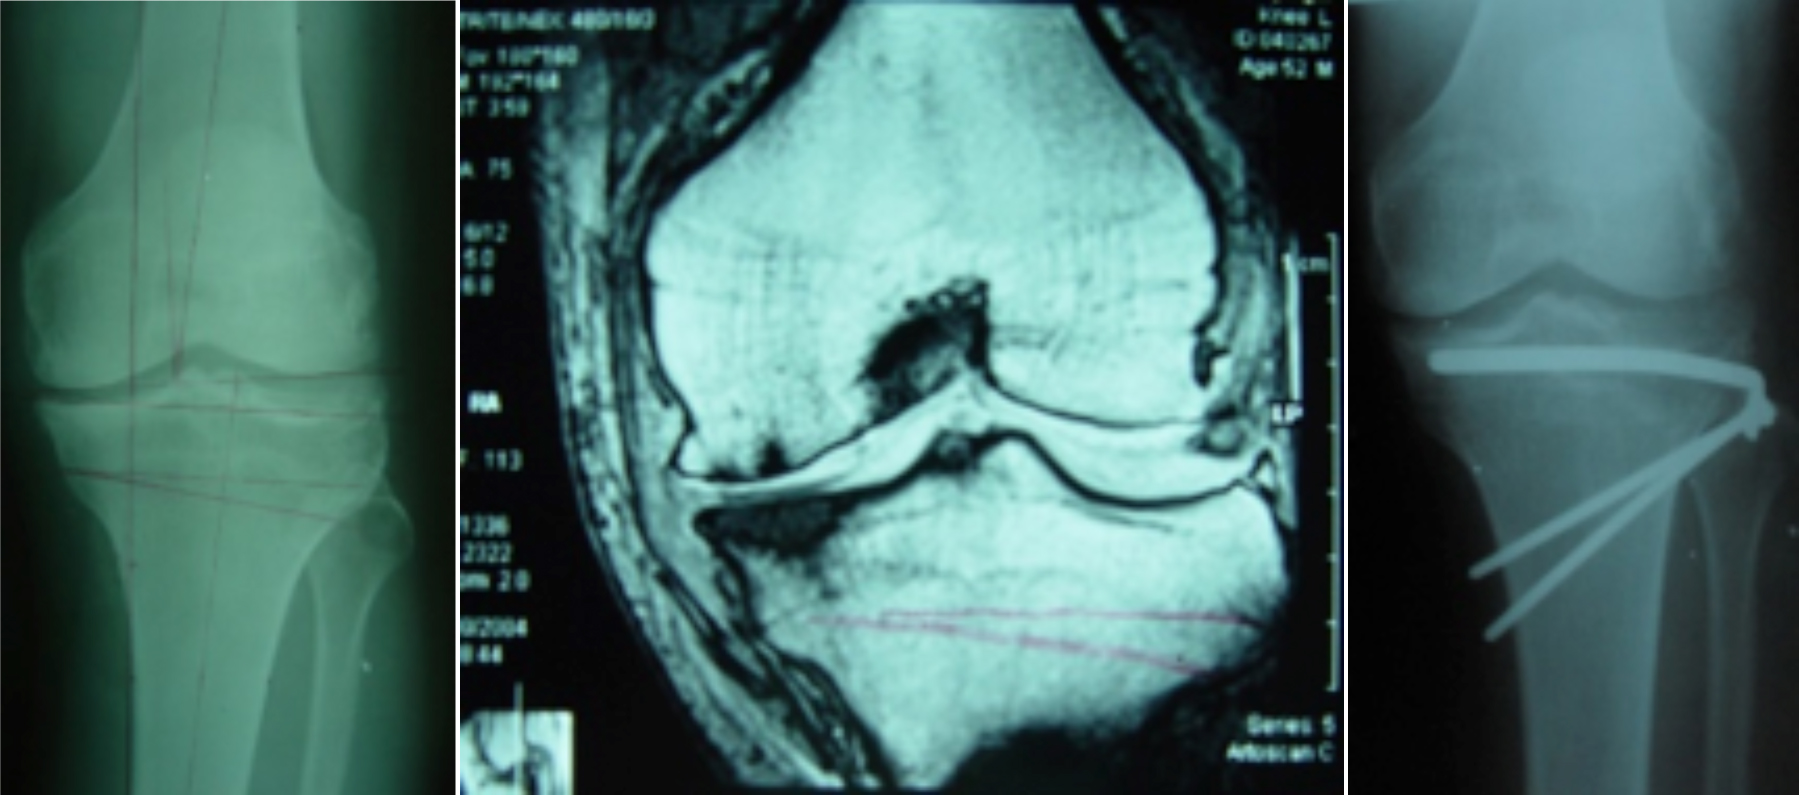

膝关节镜-半月板损伤

膝关节镜-前交叉韧带重建

膝关节镜-关节内游离体

开展关节镜下交叉韧带单、双股解剖重建技术、膝关节多韧带损伤的一期修复重建术、半月板缝合技术、骨软骨移植技术、同种异体移植治疗交叉韧带损伤、双隧道重建交叉韧带、肩关节镜下肩袖修补和SLAP损伤修补术,及肘、踝、腕、髋关节镜术。专业运动员伤病诊治技术、股骨髋臼撞击综合症、股骨头坏死阶梯治疗技术、骨软骨移植技术